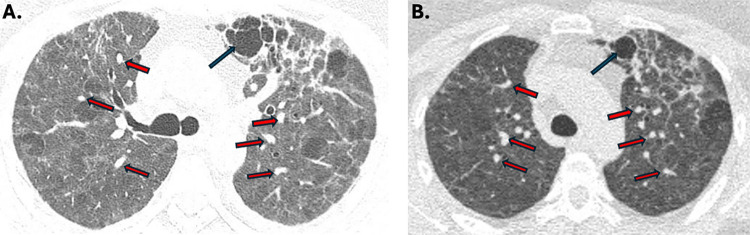

本研究报告了美洲首例由威氏曲霉引起的covid -19相关肺曲霉病(CAPA)记录病例,该病例发生在巴西圣保罗州的一个农村地区。该病例涉及一名患有COVID-19、高血压和血脂异常的52岁妇女,她在严重呼吸恶化后入院。影像学检查显示广泛的肺部受累,包括结节和空洞性病变,表明CAPA。支气管肺泡灌洗(BAL)鉴定为曲霉属(Aspergillus spp.),经benA基因测序证实该分离物为A. welwitschiae,与参考菌株CBS 139.54亲缘关系密切。基质辅助激光解吸/电离飞行时间质谱进一步验证了这一鉴定。传统上被认为是一种植物病原体,wellwitschiae最近与人类疾病(如耳真菌病)有关,并且越来越多地在呼吸道样本中检测到。然而,其与CAPA的关系在全球范围内,特别是在美洲,仍然被低估。这个病例强调了准确的真菌诊断的重要性,因为曲霉菌种类之间的重叠形态特征会阻碍临床管理。在这种情况下,welwitschiae的鉴定引起了人们对其在农业地区作为新兴病原体的潜力的关注,在这些地区,环境暴露可能会推动其流行病学相关性。鉴于越来越多的人认识到welwitschiae是一种CAPA剂,本报告强调了它在该病流行病学中的重要性及其在农业活动高的地区的潜在作用。准确识别对于指导有针对性的干预措施和解决这种新出现的真菌威胁对covid -19患者构成的公共卫生风险至关重要。

This study reports the first documented case of COVID-19-associated pulmonary aspergillosis (CAPA) caused by Aspergillus welwitschiae in the Americas, which occurred in a rural area of Sao Paulo State, Brazil. The case involves a 52-year-old woman with COVID-19, hypertension, and dyslipidemia, who was admitted following severe respiratory deterioration. Imaging tests revealed extensive pulmonary involvement, including nodular and cavitary lesions indicative of CAPA. Bronchoalveolar lavage (BAL) analysis identified Aspergillus spp. using morphological and molecular techniques, and sequencing of the benA gene confirmed the isolate as A. welwitschiae, closely related to the reference strain CBS 139.54. Matrix-assisted laser desorption/ionization-time of flight mass spectrometry further validated this identification. Traditionally recognized as a plant pathogen, A. welwitschiae has recently been implicated in human diseases, such as otomycosis, and is increasingly detected in respiratory samples. However, its association with CAPA remains underreported globally, particularly in the Americas. This case highlights the critical importance of accurate fungal diagnosis, as overlapping morphological features among Aspergillus species can hinder clinical management. The identification of A. welwitschiae in this context raises concerns about its potential as an emerging pathogen in agricultural regions, where environmental exposure may drive its epidemiological relevance. Given the growing recognition of A. welwitschiae as a CAPA agent, this report underscores its importance in the epidemiology of the disease and its potential role in regions with high agricultural activity. Accurate identification is essential for guiding targeted interventions and addressing the public health risks posed by this emerging fungal threat toCOVID-19 patients.